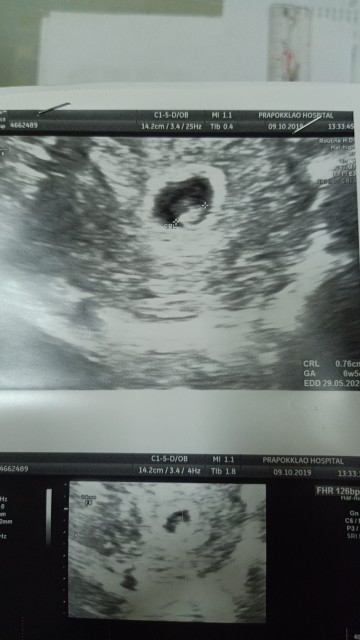

7w4d จ้า